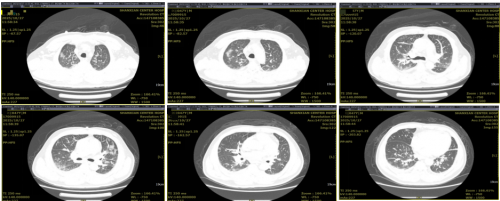

患者症状减轻,高流量氧疗湿化氧疗下氧合指数逐渐改善,下调参数,2025.11.2序贯为鼻导管吸氧。

11月3日复查胸部CT:肺内感染治疗后复查所见,较前呈吸收好转改变;双肺纤维灶、微小结节灶。